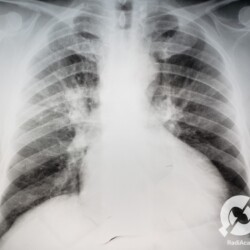

Aumento do volume cardíaco, inversão da circulação pulmonar, lesões intersticiais reticulares com linhas B de Kerley bilaterais e obliteração do seio costofrênico direito.